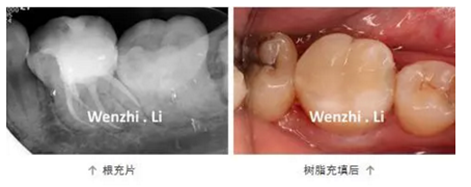

病例三 | 下頜第一磨牙彎曲根管一例

年輕女性患者因左下后牙間斷性自發(fā)性疼痛及冷熱刺激痛1個(gè)月就診,診斷為36慢性牙髓炎。局麻下,橡皮樟隔離下去腐,開髓,揭頂,可見髓腔鈣化,顯微鏡下超聲去除鈣化物,探及4個(gè)根管口,拍攝初尖銼片顯示MB根管為重度彎曲根管、DL根管彎曲極近根尖區(qū),X線片上未顯示。17% EDTA配合PathFile、Protaper NEXT 鎳鈦器械預(yù)備根管,實(shí)現(xiàn)連續(xù)錐度的根管形態(tài),5.25% NaClO沖洗,連續(xù)波熱牙膠根管充填4個(gè)根管,拍攝根充片,X線片顯示根充恰填。隔濕干燥,自酸蝕粘接,SDR+納米樹脂充填。

1.下頜第一磨牙解剖形態(tài);84%的下頜第一磨牙根管為彎曲根管,大 多數(shù)的下頜第一磨牙為DL根管彎曲,且彎曲程度不一。DL根管通常向遠(yuǎn)中頰側(cè)彎曲彎曲根管預(yù)備并發(fā)癥;

2. 預(yù)備彎曲根管技巧:器械預(yù)彎,建立直線通路;使用柔韌性及抗疲勞強(qiáng)度更好的鎳鈦旋轉(zhuǎn)器械;足量及有效的超聲根管蕩洗;連續(xù)波加壓充填技術(shù)。PathFile柔韌性好,在足量根管潤(rùn)滑劑下,可以順暢的通過根管彎曲部。Protaper NEXT 具有較好的柔韌性及抗疲勞強(qiáng)度,可降低預(yù)備彎曲根管時(shí)出現(xiàn)根管偏移的風(fēng)險(xiǎn)。